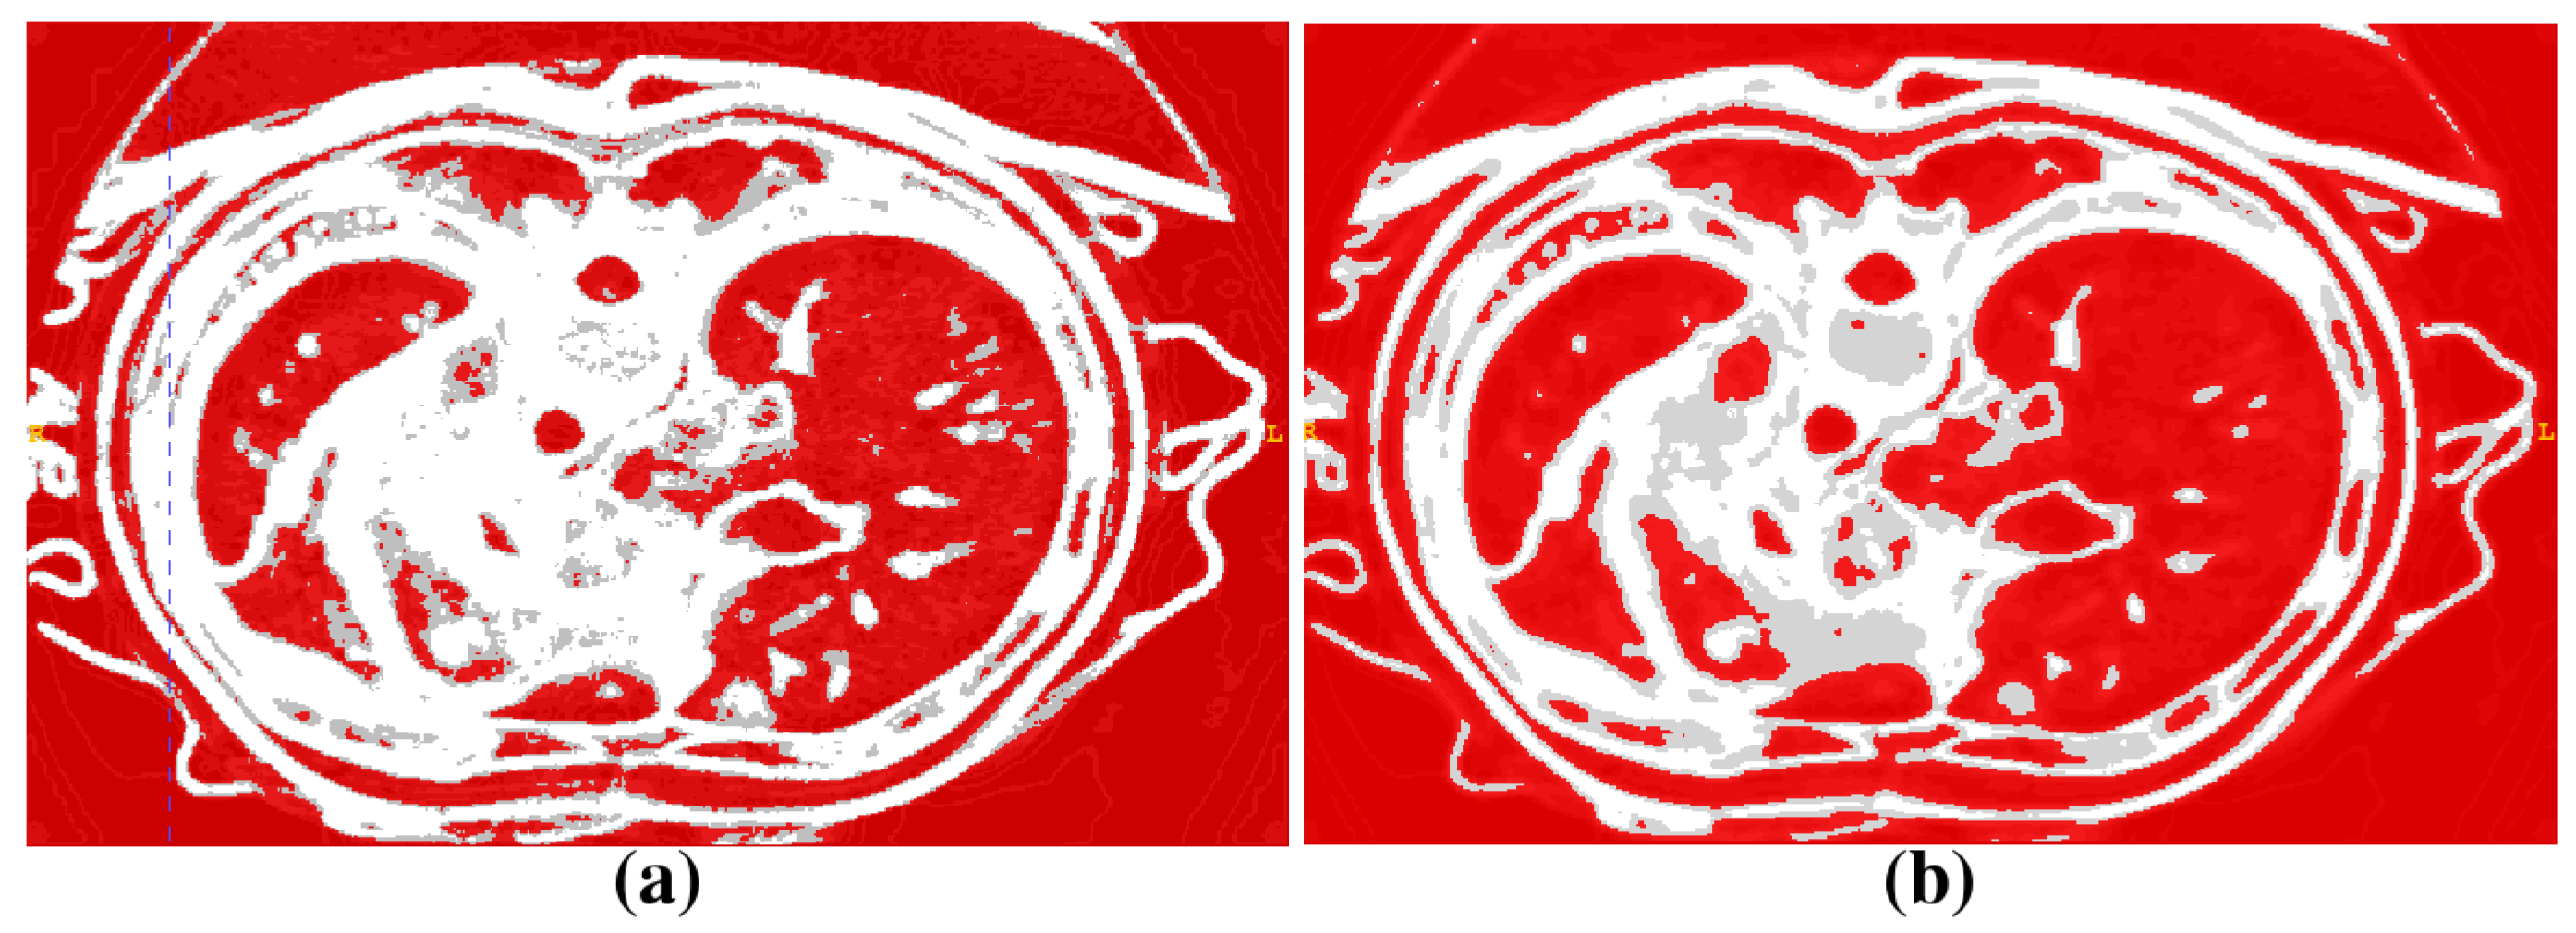

2.1. Segmentation of Abdominal Parenchymal Organs

- Pre-process and smooth the input dataset.

- Compute the spatial-dependence matrix (specified in [18]) for all voxels of the smoothed dataset.

- Compute entropy (1) for each voxel using the spatial-dependence matrix.

- Obtain the binary mask by entropy values thresholding.

- Set the seed points for organs extraction.

- Implement active contours method and extract 3D model.